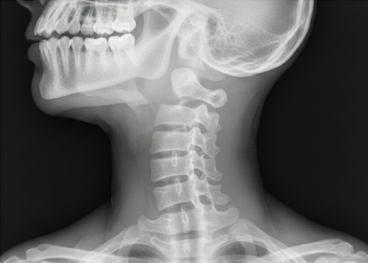

При выполнении рентгенографии шейного отдела специалист получает детализированное изображение костных структур. В первую очередь врач оценивает состояние семи шейных позвонков, их форму, контуры и взаимное расположение. На снимке четко просматриваются тела позвонков, их дуги и остистые отростки. Важнейшим аспектом диагностики является анализ межпозвонковых щелей. Хотя сами хрящевые диски на рентгене не визуализируются напрямую, об их состоянии судят по величине просвета между телами позвонков. Сужение этого пространства может косвенно указывать на развитие дегенеративно-дистрофических изменений.

Кроме того, рентген позволяет визуализировать фасеточные суставы, которые соединяют позвонки между собой. Оценка их контуров помогает выявить признаки артроза или воспалительных процессов. Также на качественном снимке видны мягкие ткани, окружающие позвоночный столб, что позволяет заподозрить наличие выраженных отеков или инородных тел, хотя для детального изучения мышц и связок обычно требуются иные методы исследования.

Одной из самых частых находок при рентгене шеи является остеохондроз. Это заболевание характеризуется постепенным разрушением межпозвонковых дисков и последующим изменением костной ткани. На рентгенограмме это проявляется в виде уплотнения замыкательных пластинок тел позвонков и появления краевых костных разрастаний, известных как остеофиты. Эти «шипы» могут раздражать окружающие ткани и сдавливать нервные корешки, вызывая характерный болевой синдром.

Рентгенография также эффективно выявляет спондилоартроз — поражение межпозвонковых суставов. На снимках врач видит сужение суставных щелей и деформацию суставных поверхностей. Важным моментом является диагностика спондилолистеза, то есть смещения одного позвонка относительно другого. Такое состояние часто становится причиной нестабильности шейного отдела, что требует особого внимания при подборе терапии или изготовлении индивидуальных ортопедических стелек для коррекции общей статики тела.

Рентген шеи незаменим при подозрении на травматические повреждения после аварий, падений или спортивных травм. Метод позволяет с высокой точностью определить наличие переломов тел или отростков позвонков, а также выявить вывихи и подвывихи. Особое внимание уделяется первому и второму шейным позвонкам (атланту и аксису), так как их повреждения наиболее опасны.

Помимо травм, рентгенологическое исследование наглядно демонстрирует нарушение естественных изгибов позвоночника. В норме шея имеет физиологический лордоз (изгиб вперед). На снимках часто обнаруживается выпрямление этого лордоза, что свидетельствует о выраженном мышечном спазме, или же патологический кифоз. Также рентген помогает диагностировать сколиоз шейного отдела — боковое искривление, которое может влиять на кровоснабжение головного мозга и общее самочувствие пациента.